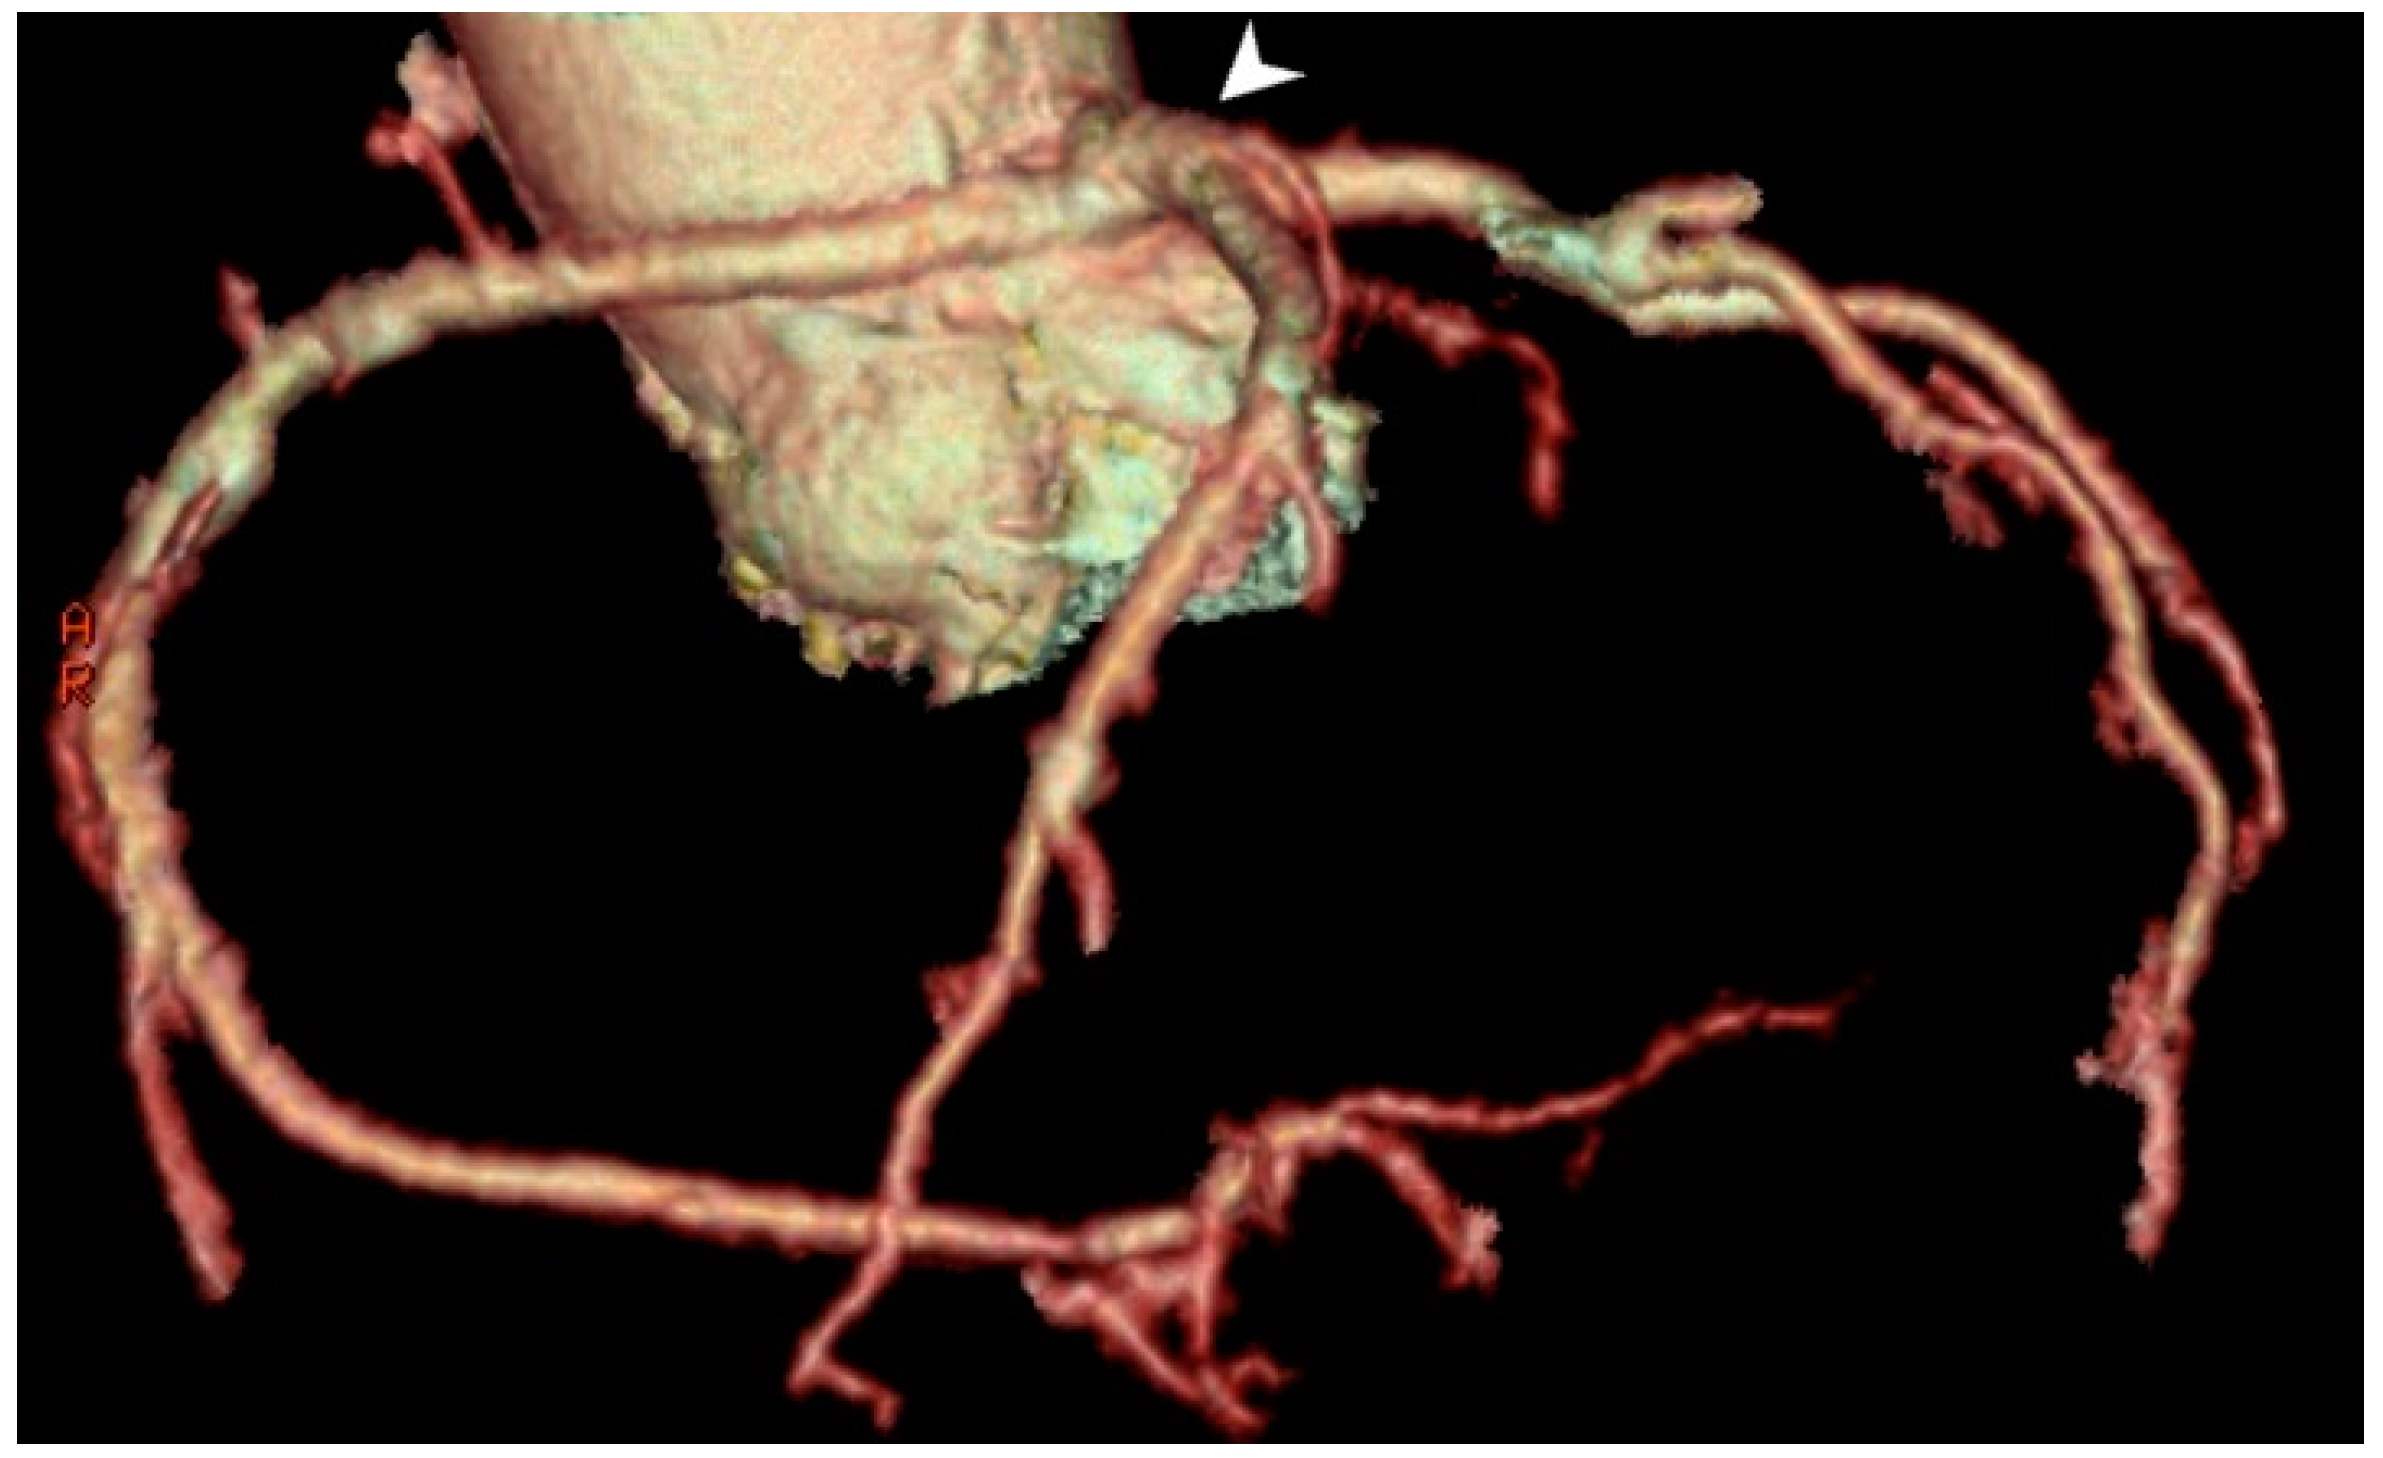

3.1.5. A Single Coronary Artery/Ostia

A single coronary artery is a congenital variety that can be classified according to its origin and number. A single coronary artery/ostia is a rare anomaly in which only one blood vessel separates from the left or right coronary sinus and splits into branches for the right and left halves of the heart (Figure 5). Patients with single CA are typically asymptomatic. In some cases, the path of one of the vessels is between the aortic bulb and the pulmonary trunk when anginal complaints occur due to pressure on the blood vessel. Other anomalies, such as the intramural course, acute take-off angle of the anomalous vessel, and a slit-like orifice, can predispose patients to anginal symptoms and sudden death during exertion.

A solitary coronary artery/ostia was first described by Hyrtl in 1841 [29], who described a single coronary artery in the absence of a left or right coronary artery; that is, the existence of a single blood vessel that supplies blood to the entire heart. Smith (1950) first classified these into the following three groups: (1) consisting of a single left or right coronary artery; (2) patients in whom an artery was isolated from one ostium and then divided into branches, one of which would cross to the opposite side of the heart and follow the path of the missing coronary artery; (3) atypical cases that could not be classified in the first or second group [30]. Surgical options include osteoplasty, coronary artery bypass grafting (CABG) of the anomalous artery, and the re-implantation of the anomalous artery into the aorta.

Figure 5. MDCT coronary angiography revealed a single coronary artery, originating from an ostium in the left sinus of Valsalva (white arrow head). This rare anomaly may range from benign to life-threatening depending on the artery’s course—especially if it passes between the aorta and pulmonary artery.